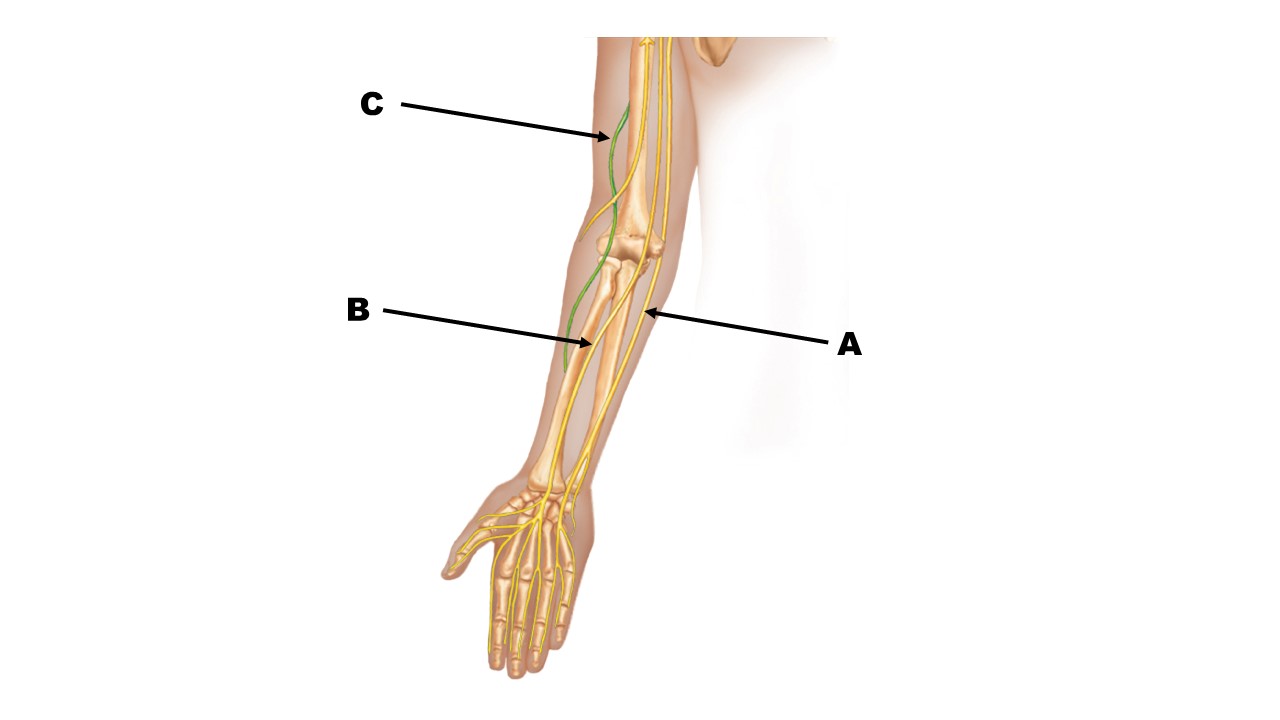

The nerve at the tip of arrow B is the _______ nerve.

The nerve at the tip of arrow A is the _______ nerve.